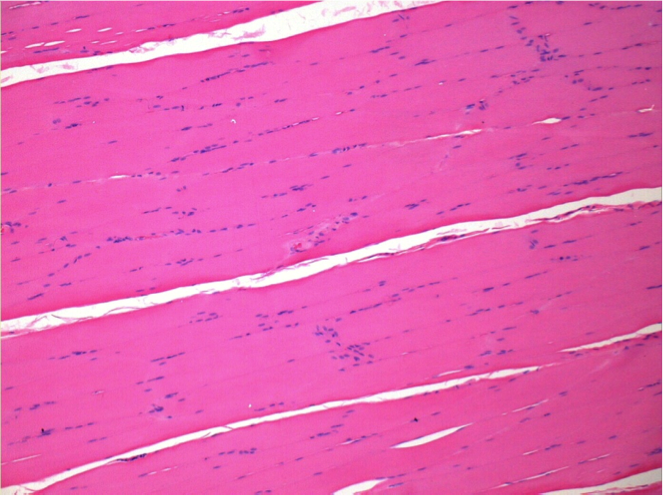

L:Pretibial-No treatment

R:Pretibial-After 0.1 ml NaCl 0.9% IM